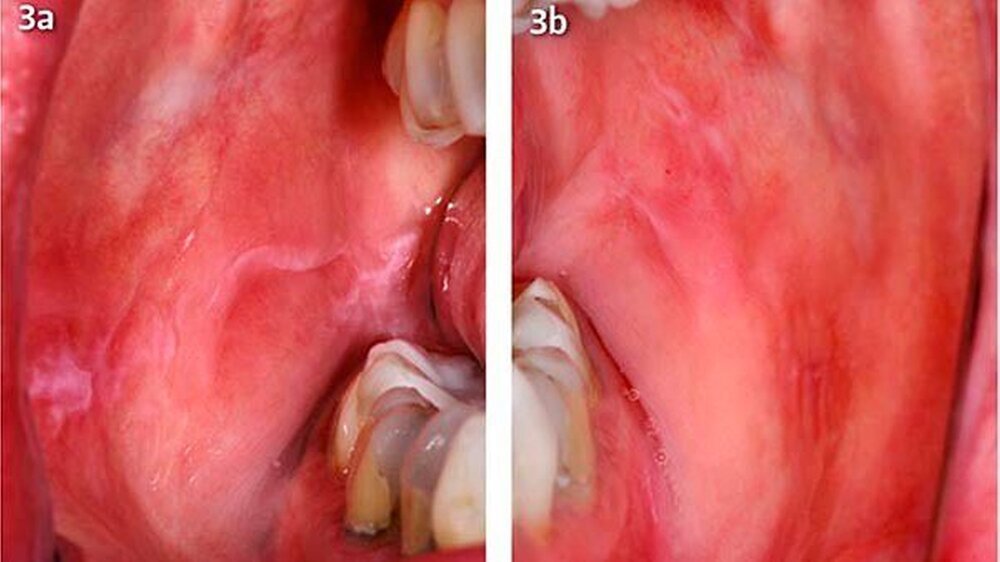

Um eine mögliche Unverträglichkeit der alternativ infrage kommenden Dentalmaterialien auszuschließen, wurde zusätzlich eine intraorale Verträglichkeit mithilfe einer speziell individuell angefertigten Schiene im Oberkiefer durchgeführt (Abb. 2). Zunächst erfolgte ein schrittweiser Austausch der Amalgamfüllungen durch provisorische Glasionomerzementfüllungen (Abb. 3a, b). Es kam zu einem deutlichen Rückgang der lichenoiden Reaktionen im Planum buccale sowie der Zungenränder.

Im Zuge der Sanierung wurde der Zahn 24 extrahiert und nach 5 Monaten ein Titanimplantat inseriert. Die Amalgamtätowierung regio 47 wurde chirurgisch exzidiert (Abb. 4). In der pathologischen Untersuchung zeigte sich ein Fettbindegewebsstück mit Nachweis von schwarz-braunem Fremdmaterial mit umgebend ausgeprägter Fibrose und Sklerose sowie herdförmiger Kalzifikation neben einer mäßiggraden chronischen Entzündungsreaktion. Die definitive Versorgung der Zähne erfolgte mit Vollkeramikkronen, die mit einem Glasionomerzement befestigt wurden.

In den Nachuntersuchungen sechs Monate nach Entfernung der Amalgamfüllungen zeigte sich ein deutlicher Rückgang der lichenoiden Effloreszenzen (Abb. 5a, b). In regio 47 distal bestand ein retikulärer Lichen planus. Die plaqueartigen Inseln im Planum buccale und die großflächigen Wickham-Streifungen sind weitgehend zurückgegangen. Die Patientin befindet sich weiterhin in einem engmaschigen Recall.